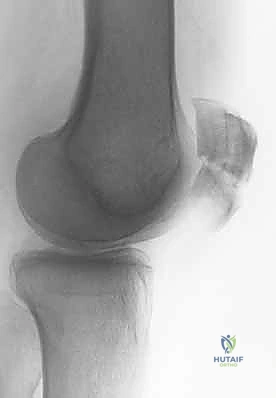

الأشعة السينية (X-rays): هي الخطوة الأولى والأساسية. يتم أخذ صور من زوايا متعددة:

- المنظر الجانبي (Lateral View): حاسم جداً لتقييم مدى تباعد أجزاء الكسر (Displacement) وعدم انتظام السطح المفصلي (Articular step-off).

- منظر السماء (Skyline View): مفيد لرؤية الكسور الطولية وتقييم التمفصل بين الرضفة وعظم الفخذ، ويتم إجراؤه إذا كانت حالة المريض تسمح بثني الركبة قليلاً.

تصنيف كسور الرضفة

يتم تصنيف كسور الرضفة بناءً على نمط الكسر ومدى تباعد الأجزاء العظمية. هذا التصنيف يوجه خطة العلاج.

| الكسر المستعرض (Transverse) | كسر أفقي يقسم الرضفة إلى جزئين (علوي وسفلي). هو النوع الأكثر شيوعاً. | قوة شد عنيفة (انقباض العضلة الرباعية) أو ضربة مباشرة. | جراحي (ORIF) إذا كان هناك تباعد > 3 ملم، تحفظي إذا لم يكن هناك تباعد. |

| الكسر المفتت (Comminuted) | تكسر الرضفة إلى ثلاث قطع أو أكثر. غالبًا ما يكون مصحوبًا بضرر كبير في الغضروف. | ضربة مباشرة قوية جداً (مثل حادث سيارة). | جراحي معقد (قد يتطلب استئصال جزئي للرضفة إذا كانت القطع صغيرة جداً). |